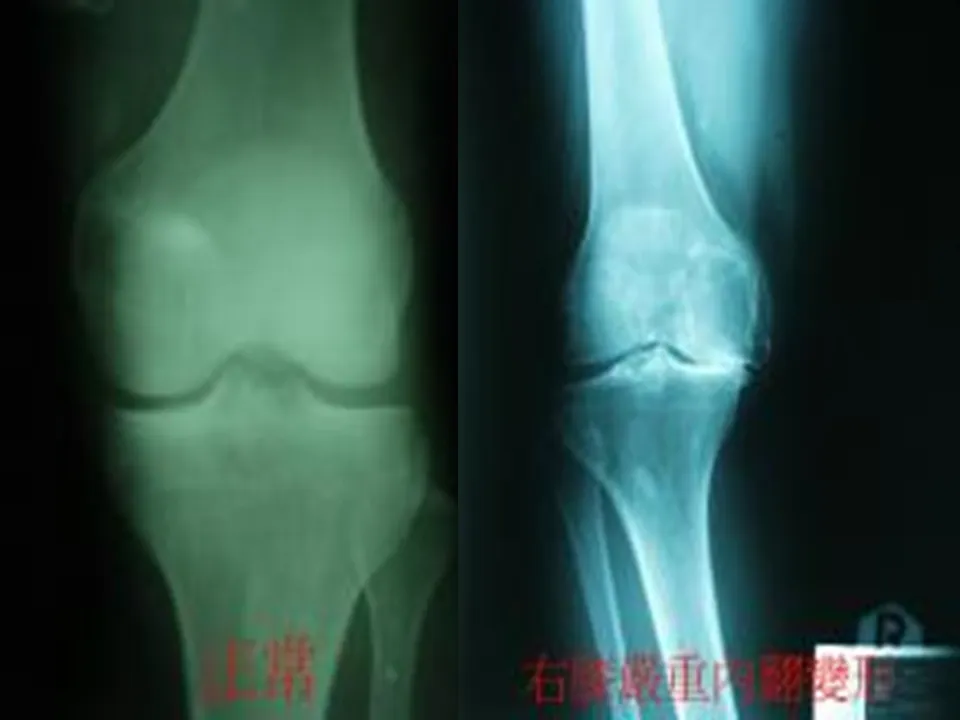

>【骨科PPT】人工膝关节表面置换术的配合

【骨科PPT】人工膝关节表面置换术的配合